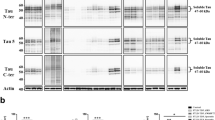

Microscopic C9ORF72 pathology in a pathological AD case. Ubiquitin (Ubi-1), sequestosome-1 (p62), ubiquilin-2 (Ubqln2), and phospho-TDP-43 (pS409/410) immunohistochemistry in the cerebellum (a, c, e, g) and hippocampus (b, d, f, h) of Case 24. Ubi-1 and p62 antibodies stain hallmark cerebellar NCIs in the Purkinje and granule cell layer, and hippocampal NCIs in the dentate fascia (a–d). Ubi-1 additionally labels normal aging pathology in the cerebellar white matter (unseen with p62), and senile plaques (SP) and neurofibrillary tangles (NFT) in the endplate and molecular layer of the hippocampus (a, b). p62 labels SP in the hippocampus (d). Ubqln2 marks cerebellar NCIs in the granule cell layer, but not in the Purkinje layer (e). In the hippocampus, the dentate contains Ubqln2-positive NCIs. The molecular layer has many immunopositive neurites and no Ubqln2-positive AD pathology (f; Fig. 4). There is no TDP-43 staining in the cerebellum and occasion TDP-43 stained NCIs in the dentate fascia (g, h). Bar = 20 μm for a, c, e, and g; 50 μm for b, d, f, and h

Subsequent investigation of other brain regions revealed TDP-43-negative inclusions characteristic of c9FTD/ALS (Fig. 3). Specifically, ubiquitin and ubiquitin-binding proteins p62 and Ubqln2 labeled frequent NCI as well as neuronal intranuclear inclusions (NII) in the granule cell layer of the cerebellum (Fig. 3a, c, e). These inclusions were negative for TDP-43 (Fig. 3g). As with other cases of c9FTD/ALS, p62 labeled more inclusions than Ubqln2 or ubiquitin, and double labeling with Ubqln2 demonstrated that the inclusions were not always co-labeled (Supplementary Fig. 2). Ubiquitin and p62, but not Ubqln2, also labeled NCI in Purkinje cells (Fig. 3a, c, e), as well as glial cells in the molecular layer of the cerebellum (data not shown). In addition to specific c9FTD/ALS pathology, ubiquitin antibodies immunolabeled age-related granular degeneration of myelin in white matter [14], and both ubiquitin and p62 antibodies labeled NFT and dystrophic neurites in SP. In the hippocampus, ubiquitin, p62, and Ubqln2 antibodies labeled NCI in the dentate fascia (Fig. 3b, d, f). TDP-43-positive NCI were sparse compared to NCI labeled with ubiquitin and p62 (Fig. 3h). In the molecular layer and the endplate of the hippocampus, SP and NFT were labeled with ubiquitin and p62 antibodies, but not Ubqln2. Rather, Ubqln2 was a sensitive marker for FTLD-C9ORF72-related dystrophic neurites in the molecular layer of the dentate fascia, endplate and CA3, which could be traced to apical dendrites of these neurons.

Evaluation of the spatial relationship between c9FTD/ALS-specific pathology, namely TDP-43-negative NCI and dystrophic neurites, and phospho-tau (PHF-1) pathology using immunofluorescence demonstrated minimal co-localization (Fig. 4a). Ubqln2-positive NCI in the dentate fascia and dendritic dystrophic neurites in the hippocampal molecular layer had no phospho-tau, whereas phospho-tau-positive NFT in the dentate fascia and pyramidal layer, and the dystrophic neurites in SP in the molecular layer of the dentate fascia were not immunoreactive for Ubqln2. In contrast, Ubqln1, a closely-related protein to Ubqln2 and known ubiquitin-binding protein associated with NFT [35] showed little immunoreactivity with the C9ORF72-related pathology (Fig. 4b), but, there was a high degree of overlap between Ubqln1 and phospho-tau immunoreactive lesions.